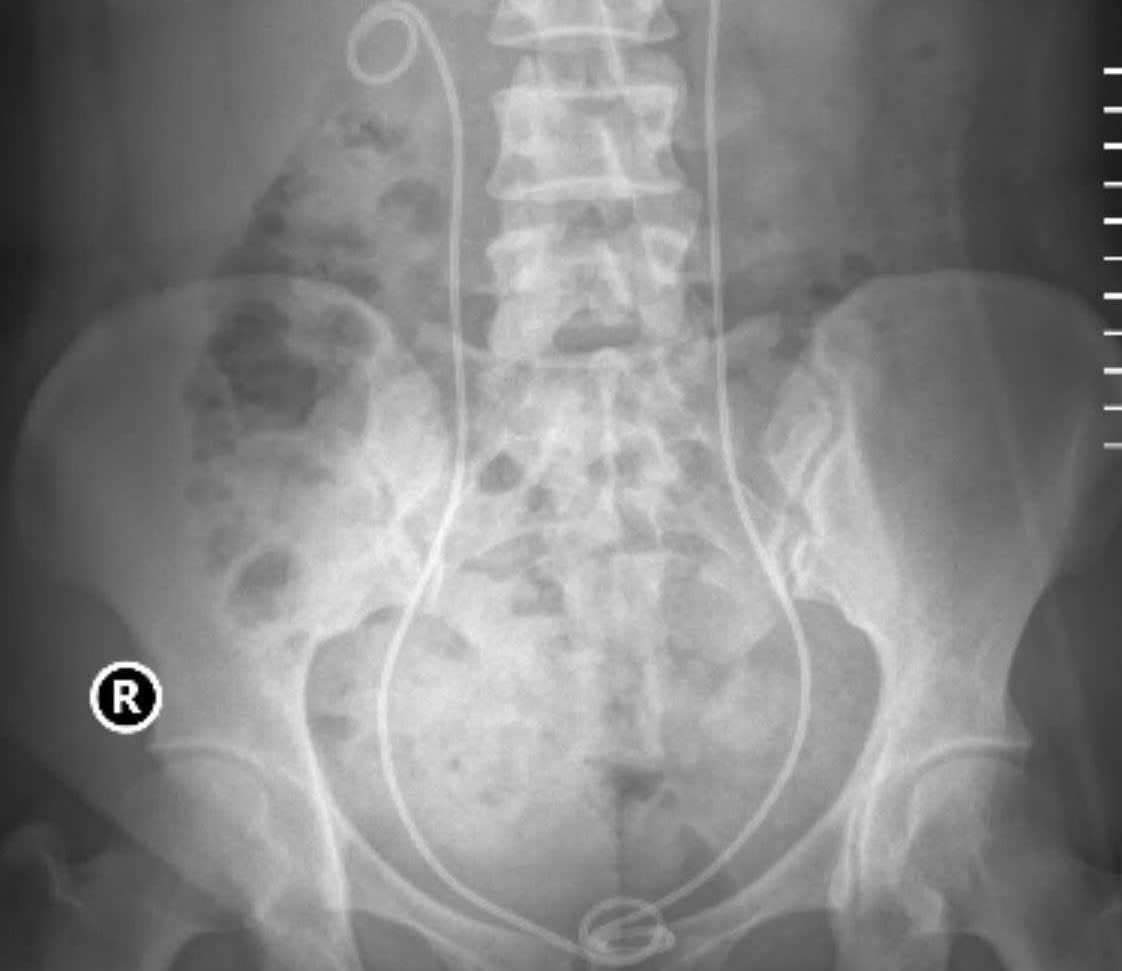

Hình ảnh Xquang sau thực hiện hai kỹ thuật tán sỏi, người bệnh hết sạch sỏi cả hai bên.

Một trường hợp gần đây đã cho thấy rõ nét hiệu quả vượt trội của sự phối hợp kỹ thuật cao trong điều trị sỏi, thể hiện năng lực chuyên môn và khả năng làm chủ kỹ thuật hiện đại của đội ngũ y bác sĩ Bệnh viện Thận Hà Nội. Người bệnh nhập viện trong tình trạng đau hông lưng dữ dội, ứ nước thận hai bên do sỏi thận và sỏi niệu quản gây tắc nghẽn. Qua thăm khám và hội chẩn chuyên môn, các bác sĩ Bệnh viện Thận Hà Nội đã quyết định tiến hành điều trị đồng thời ở cả hai bên trong cùng một đợt, phối hợp hai kỹ thuật hiện đại: tán sỏi nội soi ngược dòng bằng ống mềm (URS-F) bên phải và tán sỏi qua da đường hầm nhỏ (Mini-PCNL) bên trái. Việc lựa chọn điều trị hai bên trong cùng một đợt không chỉ giúp người bệnh giảm thiểu thời gian nằm viện, mà còn tiết kiệm chi phí và đẩy nhanh quá trình hồi phục.

Sau can thiệp, hình ảnh Xquang cho thấy hệ tiết niệu của người bệnh đã sạch sỏi hoàn toàn, điều mà nhiều phương pháp truyền thống trước đây khó có thể đạt được trong một lần điều trị duy nhất. Đặc biệt, người bệnh hồi phục tốt, hoàn toàn không còn triệu chứng đau, tiểu buốt… và có thể ra viện chỉ sau 2 ngày theo dõi hậu phẫu. Trường hợp này là minh chứng điển hình cho năng lực phối hợp linh hoạt giữa nhiều kỹ thuật điều trị sỏi tiên tiến mà Bệnh viện Thận Hà Nội đã và đang làm chủ, khẳng định vai trò trung tâm chuyên sâu hàng đầu về điều trị các bệnh lý sỏi tiết niệu phức tạp.